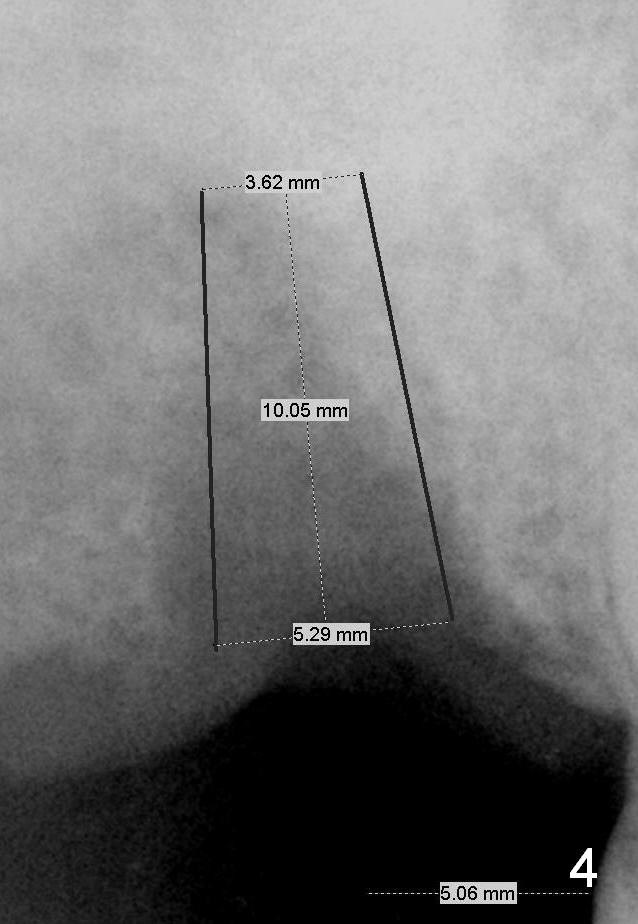

The smallest implant could be 5.3 mm (Fig.4,5). The short (10 mm, Fig.4) and long (12 mm, Fig.5) may be below and above the sinus floor, respectively.